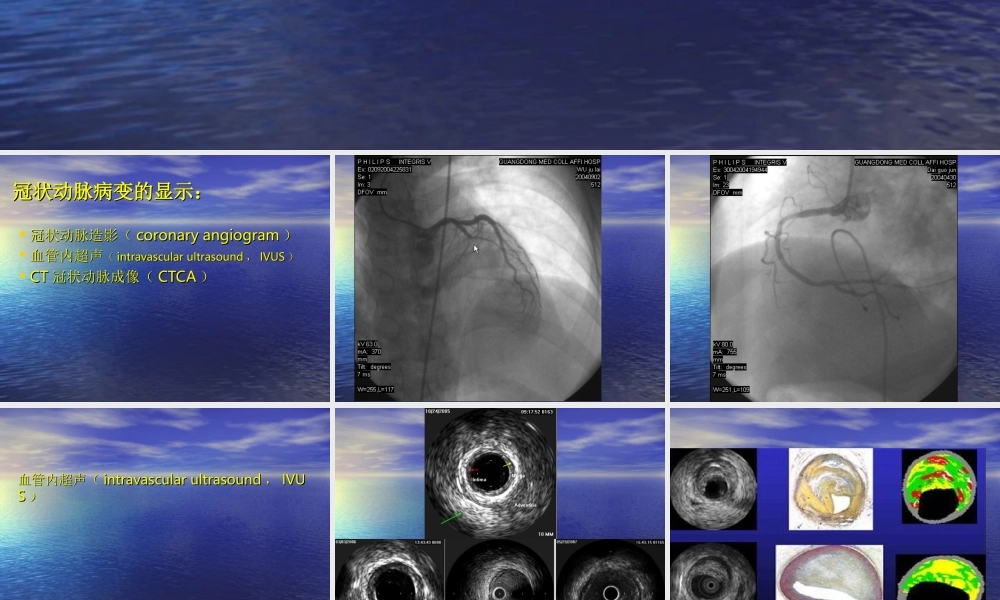

6464排螺旋排螺旋CTCT的冠状动脉成像的冠状动脉成像冠状动脉病变的显示:冠状动脉病变的显示:•冠状动脉造影(冠状动脉造影(coronaryangiogramcoronaryangiogram))•血管内超声血管内超声((intravascularultrasoundintravascularultrasound,,IVUSIVUS))•CTCT冠状动脉成像(冠状动脉成像(CTCACTCA))血管内超声(血管内超声(intravascularultrasoundintravascularultrasound,,IVUIVUSS))CTCT冠状动脉成像(冠状动脉成像(CTCACTCA))CTCT在冠状动脉病变诊断上的发展在冠状动脉病变诊断上的发展•电子束电子束CT(electronbeamcomputedtoCT(electronbeamcomputedtomographymography,,EBCT)EBCT)•多排螺旋多排螺旋CTCT((MSCTMSCT))二、冠状动脉的解剖:二、冠状动脉的解剖:•冠状动脉是供应心肌血、氧的血管,它的冠状动脉是供应心肌血、氧的血管,它的解剖形态颇多变异。在正常情况下冠状动解剖形态颇多变异。在正常情况下冠状动脉有左、右两支,分别开口于升主动脉的脉有左、右两支,分别开口于升主动脉的左、右冠状动脉瓣窦,有时从主动脉发出左、右冠状动脉瓣窦,有时从主动脉发出另一支较小的副冠状动脉。另一支较小的副冠状动脉。冠状动脉病变的定位可直接用各血管支的名冠状动脉病变的定位可直接用各血管支的名称外,可选用称外,可选用1515段分法来描述。段分法来描述。三、三、6464排排CTCT对冠状动脉病变的诊对冠状动脉病变的诊断断检查方法:检查方法:患者应无对比剂使用禁忌,患者应无对比剂使用禁忌,能屏气能屏气1010秒以上。检查时心率秒以上。检查时心率应控制在应控制在9090次次//分以下(最好分以下(最好7575次次//分以下),无严重心率失分以下),无严重心率失常,必要时可使用药物控制。常,必要时可使用药物控制。先行平扫(不使用对比先行平扫(不使用对比剂),图像用于钙化积分分析。剂),图像用于钙化积分分析。增强时使用双筒高压注射器注射增强时使用双筒高压注射器注射对比剂,注射流率对比剂,注射流率4-5ml/s4-5ml/s,因,因此,病人应的较好的外周静脉条此,病人应的较好的外周静脉条件。件。对比剂最好采用对比剂最好采用370g370g以上浓度非离子型对比剂。可采以上浓度非离子型对比剂。可采用用BolustrackingBolustracking或或TestBolTestBolusus两种方式追踪最佳扫描时机。两种方式追踪最佳扫描时机。通常采用后置心电门控,通常采用后置心电门控,60-8060-80%%时相重建(时相重建(P...